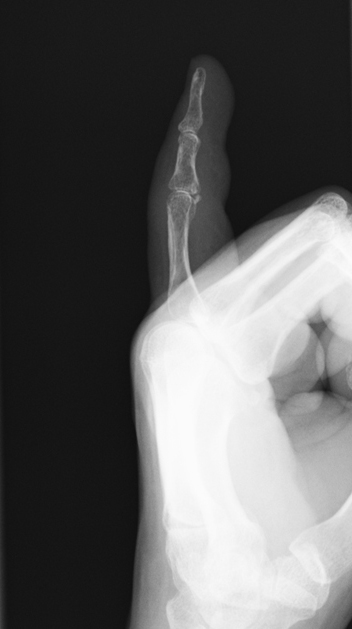

私の場合は骨折した部分がこんなことになっていて……

それにしても、ぷっくりした小指ですねえ……

われながらかわいいです。赤ちゃんの手みたいです。

って、レントゲンを見て思うことじゃないですね。(笑)

患部をアップにするとこんな感じ……(写真は小さくてすみません)